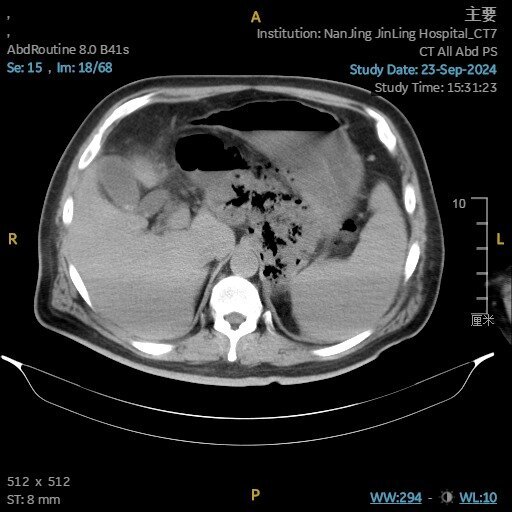

患者男性,60歲,哈爾濱人,急性重癥膽源性胰腺炎在當(dāng)?shù)刂委熞粋€(gè)月!反復(fù)發(fā)熱,胰腺全部壞死,最高39度!后轉(zhuǎn)入我院!入院ct提示整個(gè)左上腹腹膜后壞死,巨大膿腔伴感染!入院后第三天行手術(shù)清除壞死組織,術(shù)后患者體溫正常,恢復(fù)良好!患者住院35天,雙套管更換為引流管后,康復(fù)出院,回家休養(yǎng)!